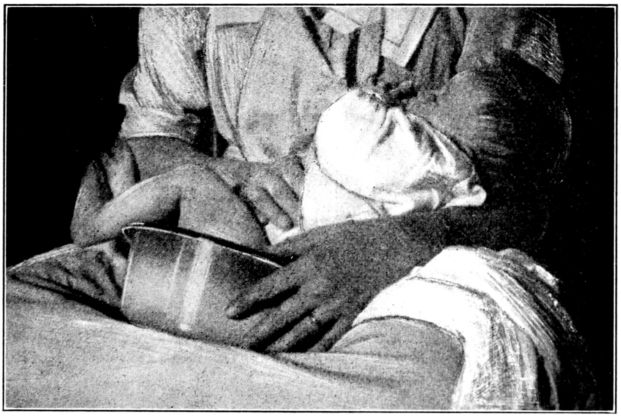

| 103. | Giving chloroform for obstetrical anæsthesia | 287 |

| 104, 105. | Giving ether for obstetrical anæsthesia | 289, 290 |